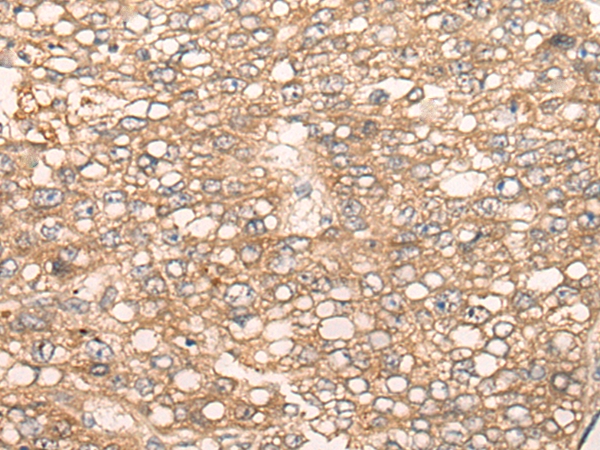

图片:

The image on the left is immunohistochemistry of paraffin-embedded Human liver cancer tissue using 46671(SLC5A8 Antibody) at dilution 1/25, on the right is treated with synthetic peptide. (Original magnification: x200)

,

The image on the left is immunohistochemistry of paraffin-embedded Human esophagus cancer tissue using 46671(SLC5A8 Antibody) at dilution 1/25, on the right is treated with synthetic peptide. (Original magnification: x200)